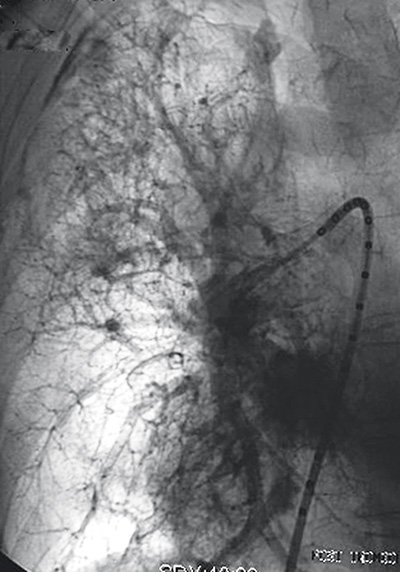

Att återställa lumen av förträngda lungartärer (Figur 2) är ett annat exempel på en relativt ny interventionell, palliativ behandling för att förbättra saturationen och minska behov av kirurgi och/eller slutenvård för patienten [4].

Figur 2. Av tumör förträngd höger arteria pulmonalis (datortomografi) öppnad med stent (arteriogram).